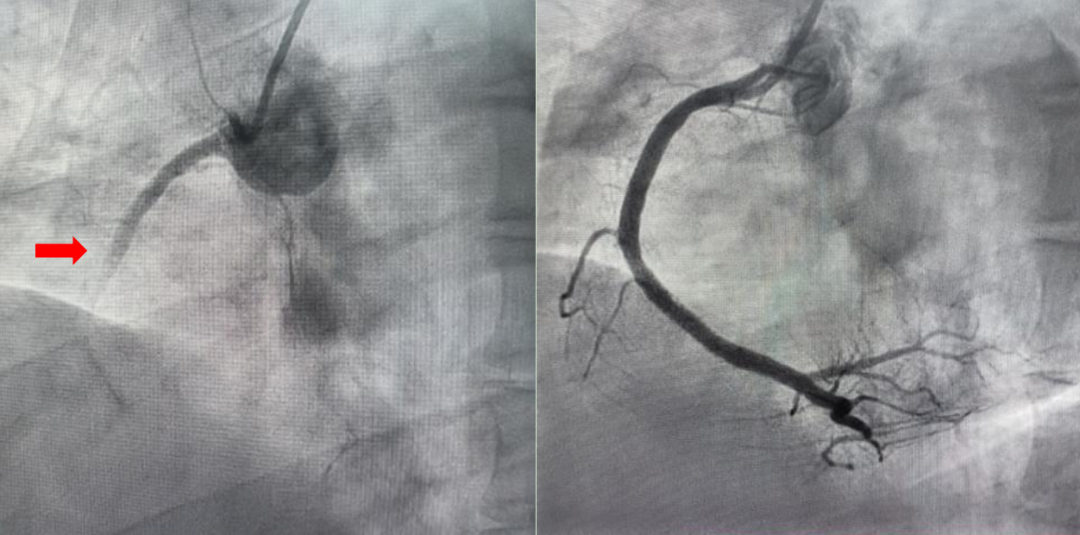

最终,在心内科介入团队协助下,深港两地专家医护密切配合,仅用 27 分钟即成功打通闭塞的右冠状动脉,成功「拆弹」,将这位年轻患者从死亡边缘拉了回来。

○ 技术精湛,专业快速:经验丰富的心内科介入团队,能够迅速完成冠状动脉造影,精准定位病变,实施球囊扩张、支架植入或血栓抽吸,以最快速度恢复患者血流。